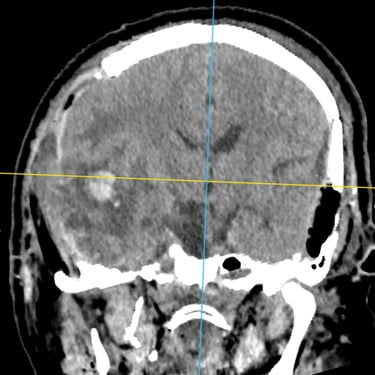

TEC Severo: Craneotomía Descompresiva Hemisférica y Evacuación de Hematoma Extradural

El traumatismo encéfalo craneano (TEC) severo es una emergencia neurológica que puede comprometer rápidamente la vida del paciente. Cuando existe edema cerebral difuso y hematomas asociados, el tratamiento quirúrgico oportuno es fundamental. La craneotomía descompresiva hemisférica derecha permite reducir la presión intracraneal y prevenir daño cerebral secundario, mientras que la craneotomía temporal izquierda con evacuación de hematoma extradural (HED) elimina el efecto de masa local. Este abordaje combinado busca preservar la perfusión cerebral, estabilizar al paciente y mejorar el pronóstico neurológico en situaciones críticas.